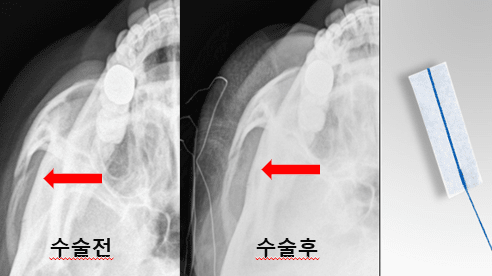

박 과장은 수술 전 단계에서부터 기존과는 다른 접근을 시도했다. 방사선에 식별 가능한 cottonoid(수술용 거즈)를 환자의 얼굴 표면 특정 위치에 부착한 뒤 X-ray 촬영을 시행해, 피부 표면 기준과 골 구조 간의 상대적 위치를 동시에 시각화한 것이다.

이 방법을 통해 단순 영상이 아닌, 실제 수술 중 조작해야 할 골절 부위의 방향성과 깊이감을 직관적으로 파악할 수 있었다. 이후 수술 중에도 동일한 기준점을 활용한 반복적인 X-ray 확인으로, 전후 및 상하 위치를 정밀하게 보정하며 환원을 진행했다.